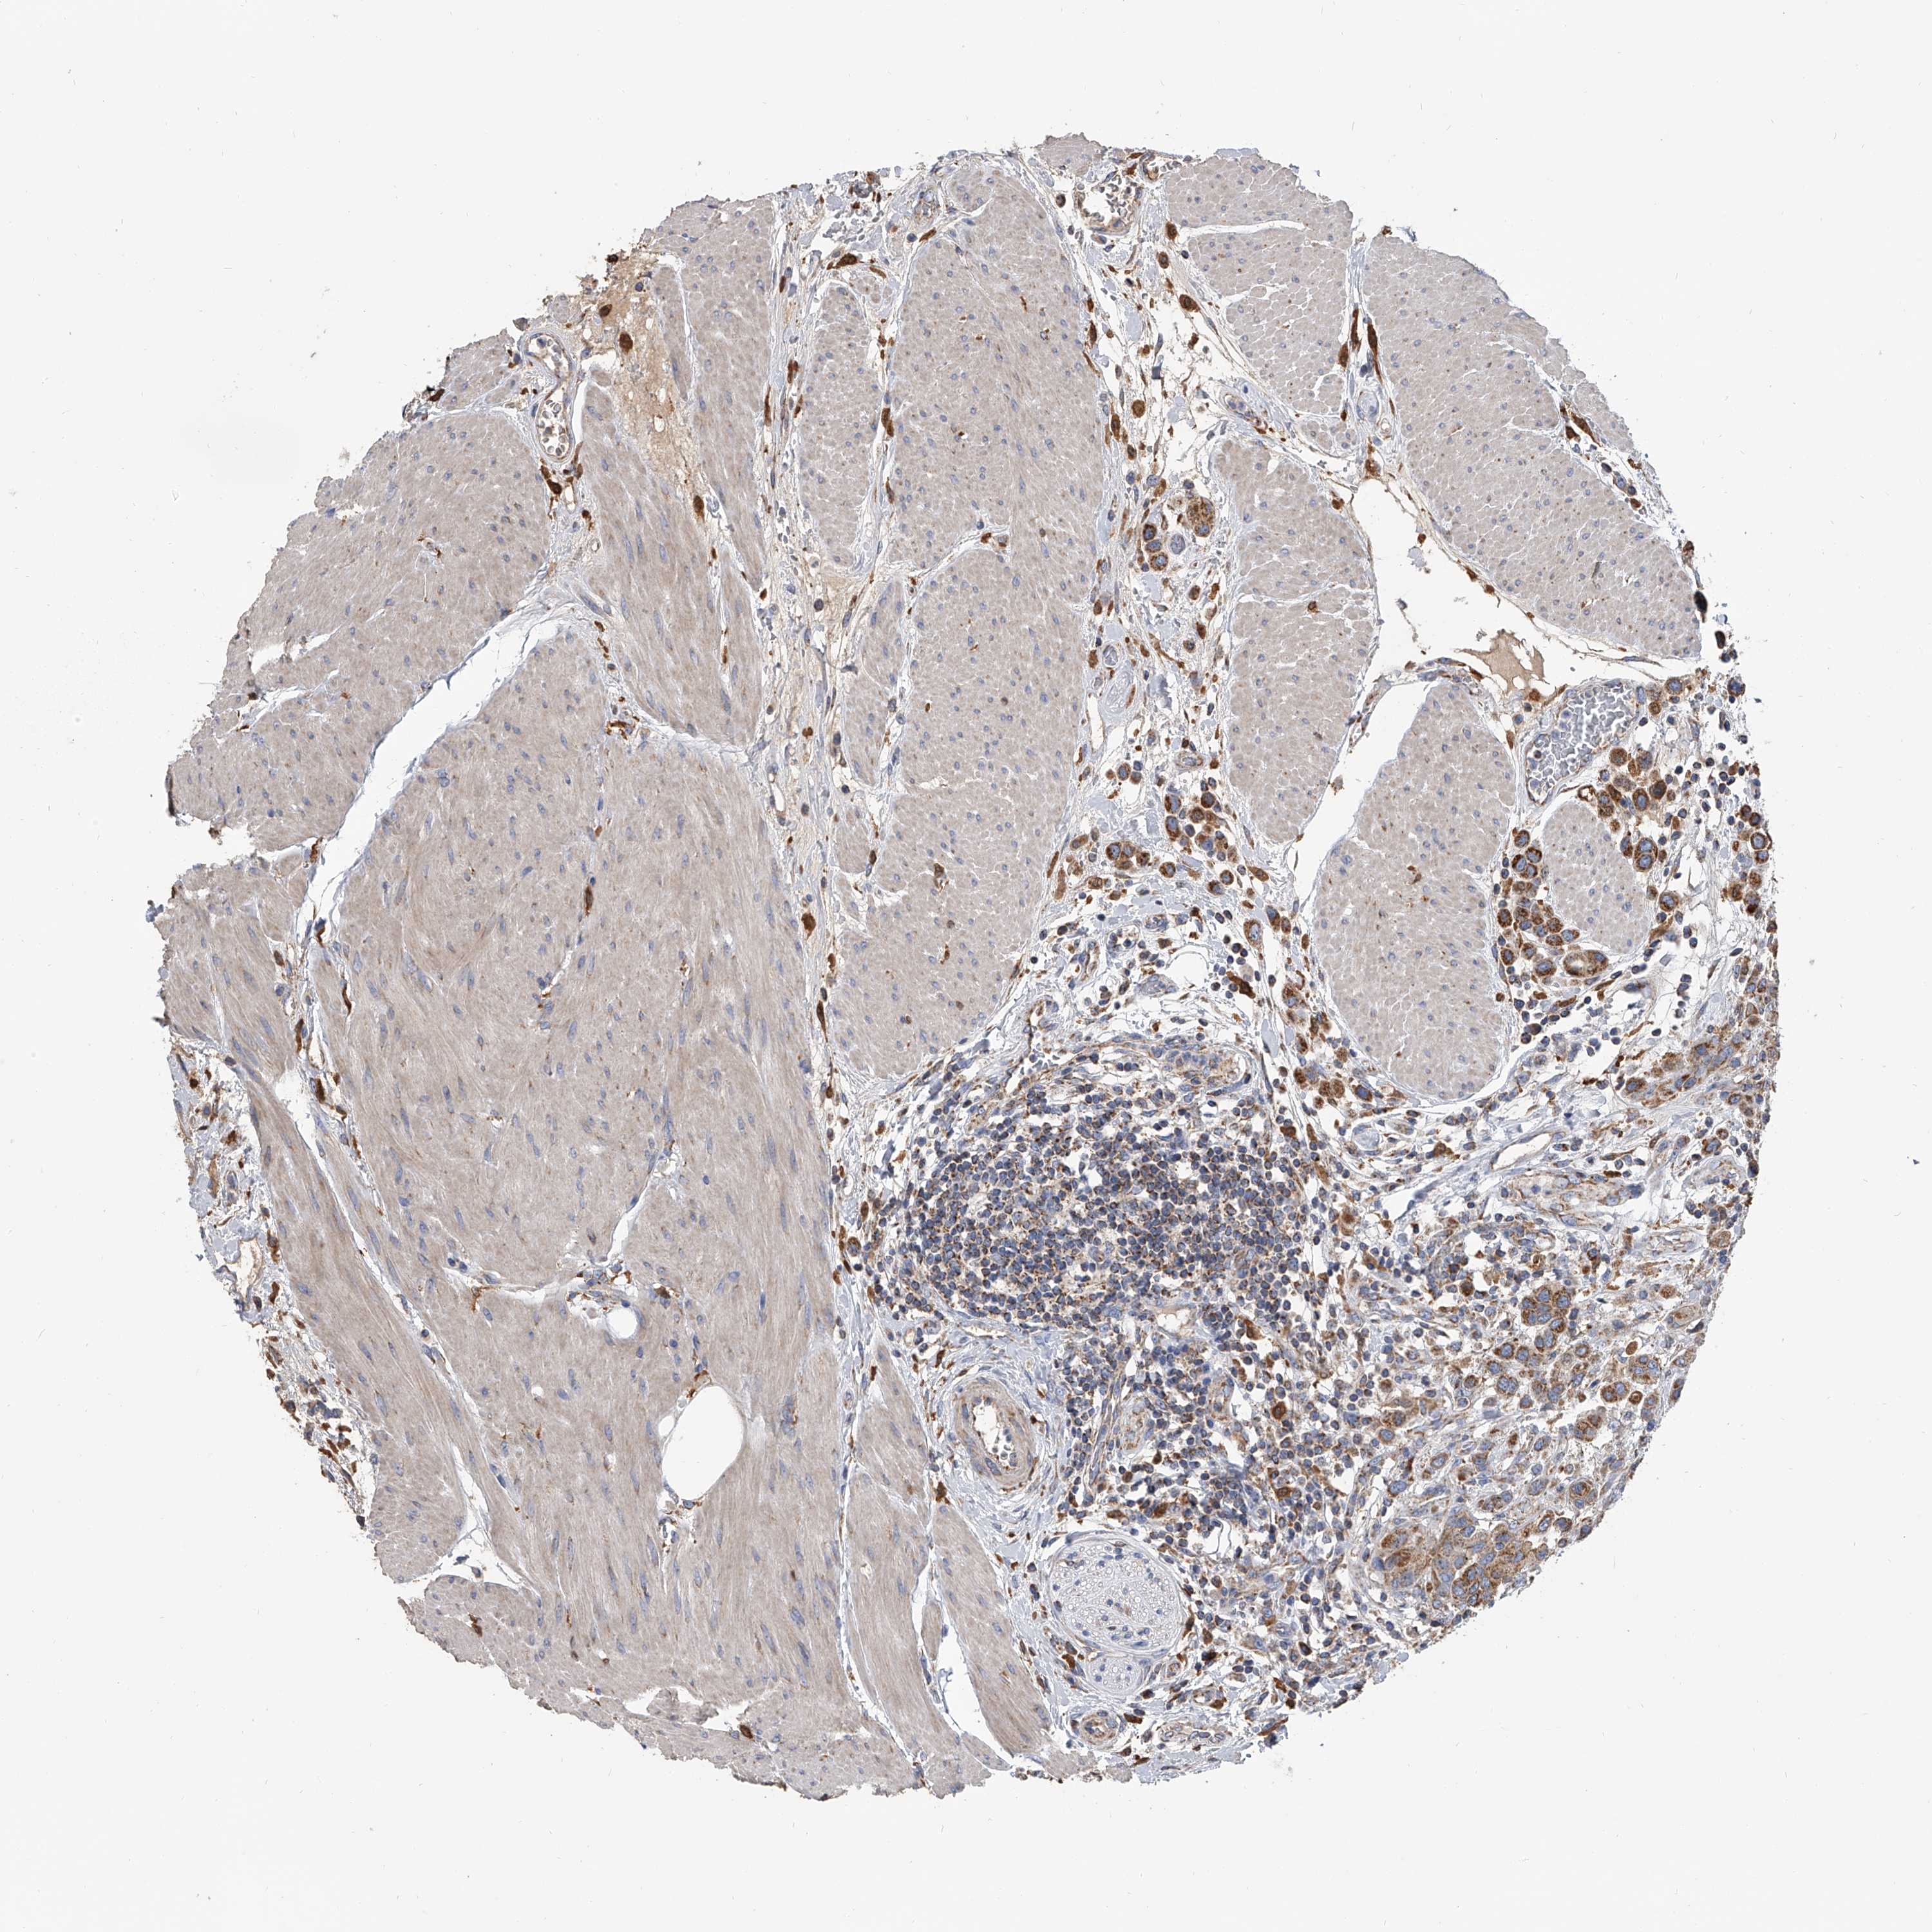

UROTHELIAL CANCER - Protein expressioni

A mouse-over function shows sample information and annotation data. Click on an image to view it in a full screen mode. Samples can be filtered based on level of antibody staining by selecting one or several of the following categories: high, medium, low and not detected. The assay and annotation is described here.

Note that samples used for immunohistochemistry by the Human Protein Atlas do not correspond to samples in the TCGA dataset.

Antibody stainingi

Antibody staining in the annotated cell types in the current human tissue is reported as not detected, low, medium, or high, based on conventional immunohistochemistry profiling in selected tissues. This score is based on the combination of the staining intensity and fraction of stained cells.

Each image is clickable and will lead to virtual microscopy that enables deeper exploration of all samples and also displays staining intensity scores, fraction scores and subcellular localization as well as patient and tissue information for each sample.

Antibody HPA030594

Antibody HPA055589

Antibody CAB033542

Staining

High

Medium

Low

Not detected

Intensity

Strong

Moderate

Weak

Negative

Quantity

>75%

75%-25%

<25%

None

Location

Nuclear

Cytoplasmic/membranous

Cytoplasmic/membranous,nuclear

Urothelial carcinoma, Low grade

Urothelial carcinoma, High grade

Urothelial carcinoma, NOS